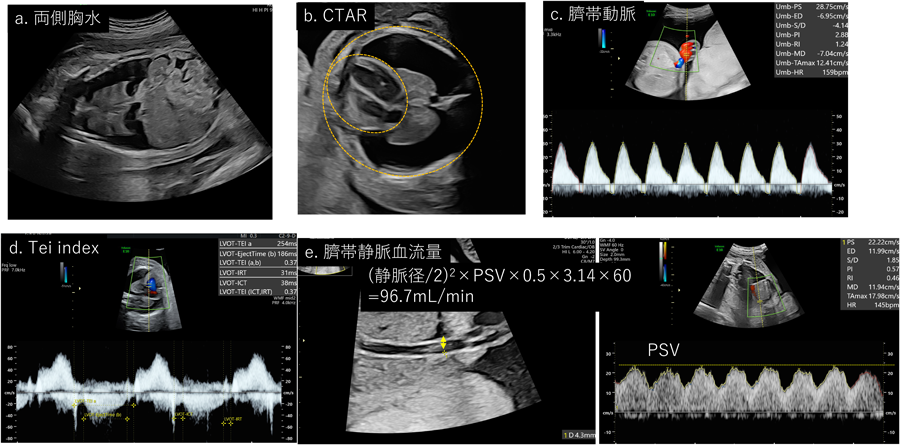

心拡大の評価

一番簡易に行えるのが心拡大の評価である.スクリーニングとして使用できるのがTCD(total cardiac dimension; Fig. 1a)である.三尖弁と僧帽弁の付着部位の心外膜外側を直線的に計測する.妊娠22週以降ではほぼ週数mmと考えることができるため簡易に利用される.経時的な心拡大の評価には心胸郭面積比CTAR(cardio-thoracic area ratio; Fig. 1b)が適している.心臓の面積は心外膜のトレースを,胸郭の面積は皮膚や筋肉を含まない肋骨や脊柱を含む部分をトレース(あるいはellipse法)で計測する.正常値は20~35%である.

Fig. 1 心拡大の評価

CTAR, cardiothoracic area ratio; TCD, total cardiac dimension

胎児の高拍出性心不全の場合,心拡大がきっかけとなって原因となる疾患が診断されることもある.胎児貧血が原因となる場合にはMCA-PSVの上昇を認める.動静脈奇形や血管腫,仙尾部奇形腫などは原因となる部位にカラードプラで豊富な血流を認める.高拍出性の場合には心不全といいながらも胎児心機能自体は保たれていることが多い.そのため代償できている間は心機能の評価項目に変化は認めない.CCOが症状の進行に鋭敏といわれていて,700–800 mL/min/kgを超えてくると胎児水腫のリスクが上昇する18).胎児の全身状態を評価する目的で静脈管のPIの上昇が参考になるという報告もある19).SCTの検討では下大静脈の増大(>6 mm)や600 mL/min/kg以上のCCOの増大が早期での心不全を検出できる可能性がある20). Fig. 6にAltman type IのSCTの症例を提示している.本症例は妊娠19週で腫瘍体積/胎児体重比が0.34(>0.12)であり,予後不良が予測されていた(Fig. 6a).妊娠25週でCTAR=51%, CCO>800 mL/min/kg, IVC=5.9 mm(Fig. 6b, c)であり,左室のMPIをはじめとした心機能や胎児の動静脈血流は保たれていた(Fig. 6d, e)が,ちょうどこの時点から皮下浮腫を認め始め,胎児水腫の傾向を呈した.

Pediatric Cardiology and Cardiac Surgery 40(2): 103-112 (2024)

Fig. 6 高拍出性心不全(仙尾部奇形腫)の一例

CCO=総心拍出量,IVC=下大静脈.CTAR, cardiothoracic area ratio

原発性胎児両側胸水

原発性両側の胎児胸水(Fig. 11a)の場合,心外腔の著しい圧迫によりCTARは縮小する(Fig. 11b).心機能はfilling timeの短縮や循環不全に伴う動静脈ドプラの変化を認める.心機能自体は保たれるものの,胸腔内圧の上昇のためか循環虚脱が引き起こされるといわれており,終末期の現象として臍帯静脈還流量(UV flow volume: UVFV)の著しい減少を認めることがある.UVFVは(臍帯静脈径(cm)/2)2×臍帯静脈最大血流速度(cm/s)×0.5×3.14×60で計測されるが30),推定体重で補正した平均値は週数によらず110 mL/min/kgと報告されている.そして約2.5%centileである50 mL/min/kg以下を低容量流入性の循環虚脱を疑っていき,胎児治療を行っても効果が得られない可能性があるといわれている31)Fig. 11に示した症例は両側胎児胸水を認め,著明な皮下浮腫と腹水を認めており,UAの逆流(Fig. 11c)を認めていたものの心機能は保たれており,Tei indexやfilling patternも2層性で保たれていた(Fig. 11d).UVFVは97 mL/min/kgであり(Fig. 11e),胎児胸腔羊水腔シャントによる胎児治療を施行し,症状が改善した一例である.

Fig. 11 原発性胎児胸水

CTAR, cardiothoracic ration; PSV, peak systolic velocity